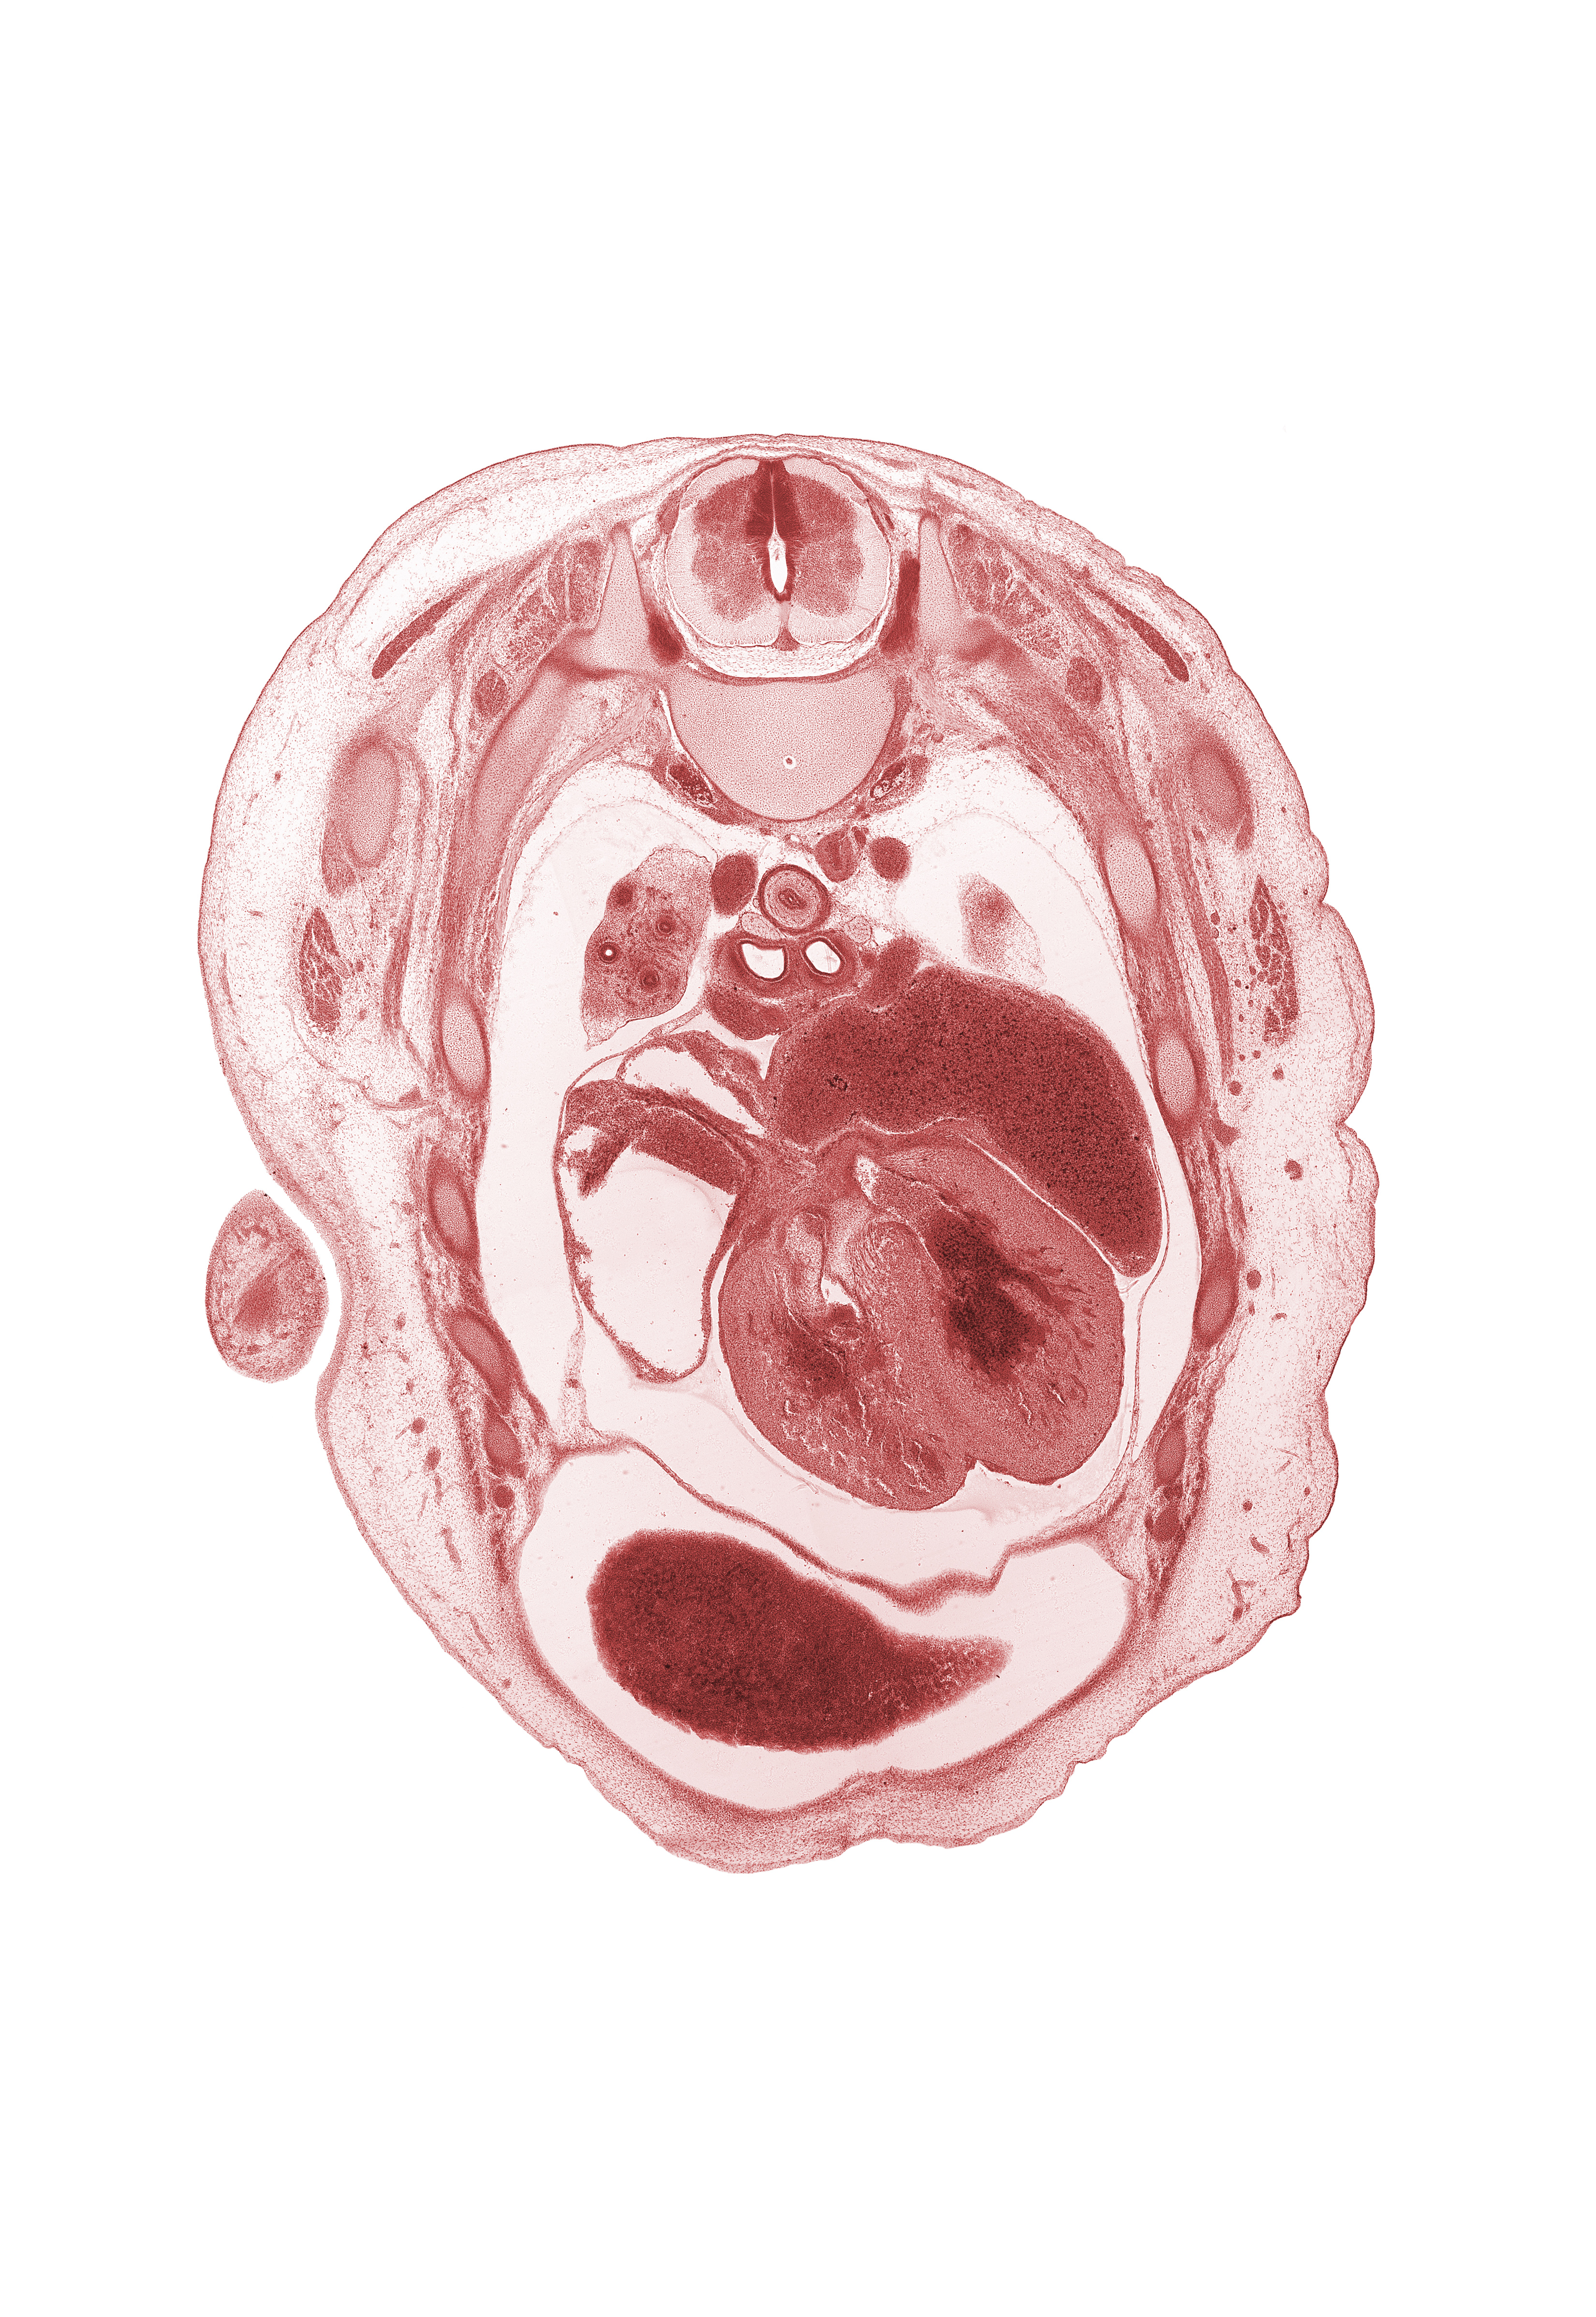

Carnegie Embryo #462 | Location: 3-04-03

Keywords: T-3 spinal ganglion, T-3 spinal nerve, aorta, apex of upper lobe of left lung, auricle of right atrium, central tendon of diaphragm, interventricular foramen, interventricular septum, latissimus dorsi muscle, left atrium, left horn of sinus venosus, left vagus nerve (CN X), primary bronchus, pulmogenic coat, rib 4, rib 6, rib 7, right lobe of liver, right vagus nerve (CN X), superior vena cava, upper lobe of right lung

Source: The Virtual Human Embryo.